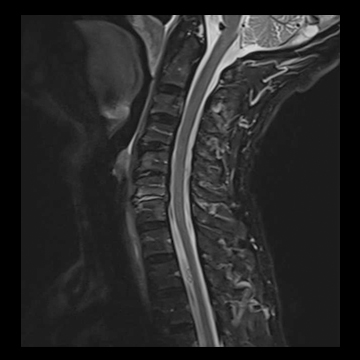

頚椎

T1 TSE, 384 matrix,

T2 TSE, 384 matrix,

T1 TIRM, 320 matrix,

全脊椎

T1 TSE, 448 matrix

T2 STIR, 384 matrix,